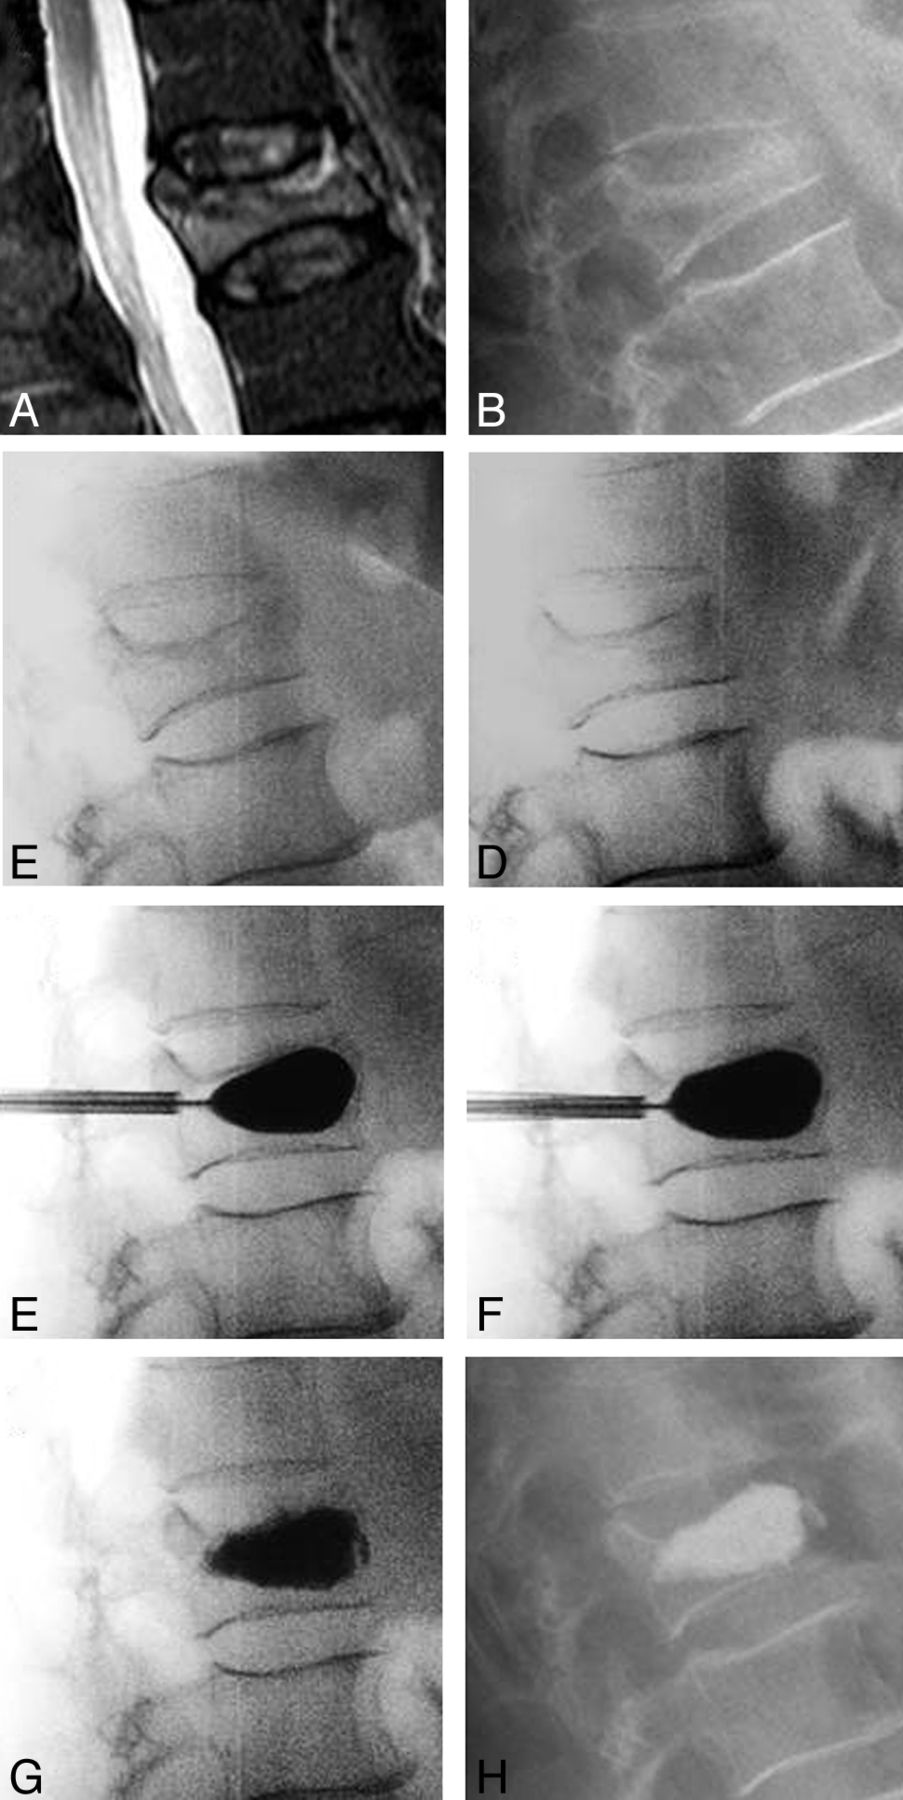

Figure 6 is an illustrative case in which there was no postural reduction at T7; the 73-year-old female patient was randomized to the IBTF group. The first balloon inflation was poor, had an irregular inflation pattern (119 [right] and 75 [left] PSI and 2.0 [right] and 1.0 [left] mL volume), and provided no angular-deformity correction. After curette use and a second balloon inflation, the result was a more uniform fill (119 [right] and 96 [left] PSI and 2.0 mL, bilateral) with deformity correction. There was 2.4° of correction overall at T7 in the standing postoperative measurement (the inferior T8 was treated within 30 days of initial treatment).

Case illustration of a nonmobile fracture. A, Preoperative standing x-ray. B, Intraoperative postural reduction with a bolster. C, Intraoperative first balloon inflation. D, Intraoperative curette and second balloon inflation. E, Intraoperative cement placement. F, Postoperative standing x-ray.